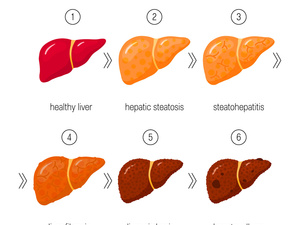

年龄是影响夫妻生活频率的一个重要因素。随着年龄的增长,男性和女性的性需求和欲望也会发生变化。年轻夫妻往往欲望比较旺盛,而随着年龄的增长,夫妻们可能会经历生理和心理上的变化,从而影响他们的夫妻生活频率。

随着年龄的增长,夫妻们的夫妻生活频率可能会发生变化。这是因为随着年龄的增长,男性和女性的身体和生理状况都会发生变化,从而影响他们的欲望和性需求。

对于男性来说,随着年龄的增长,男性的睾丸会逐渐缩小,睾丸中的睾酮水平也会下降。这可能导致男性的欲望和性需求下降。此外,年龄增长还可能导致男性出现阳痿和性功能障碍等问题,从而影响他们的夫妻生活频率和质量。

随着女性年龄的增长,她们的卵巢功能会逐渐减弱,导致排卵的频率减少,同时雌激素和孕激素水平也会下降。这些生理变化可能会影响女性对性的渴望和需求,可能导致她们在夫妻生活中频率和质量上的变化。此外,这些变化还可能导致私处干燥和不适等问题的出现。